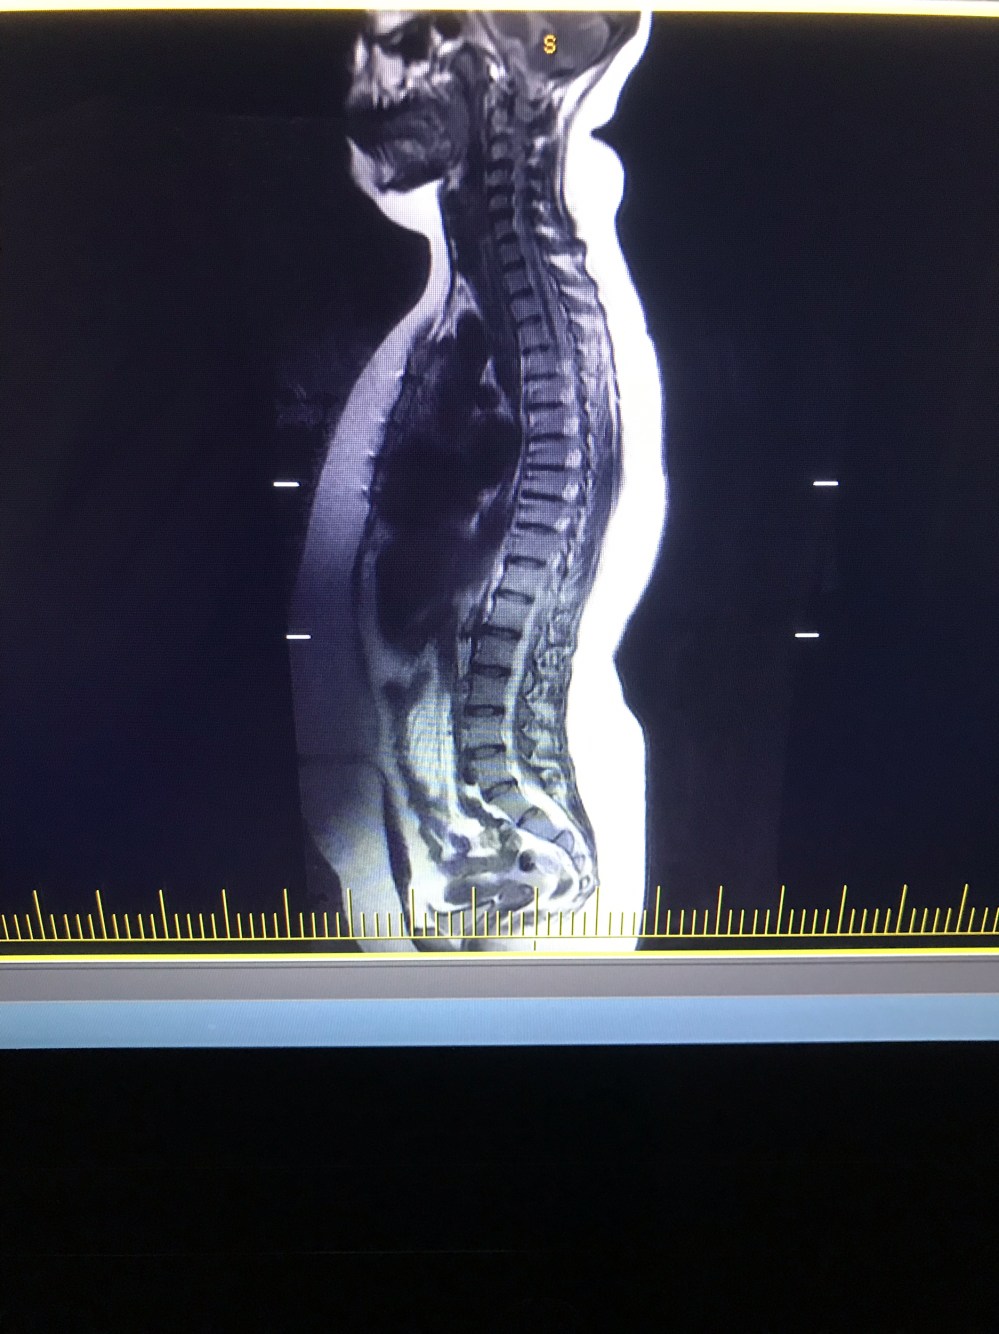

- MRI